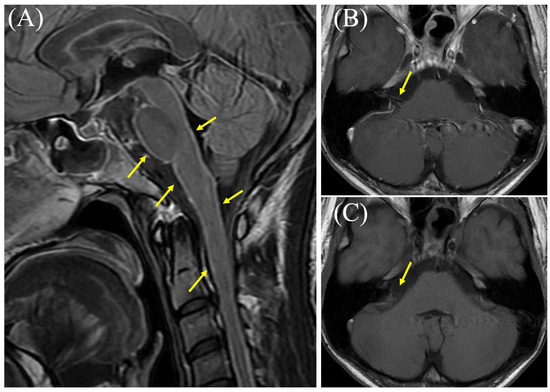

Introduction: Brain abscess is defined as a suppurative collection resulting from hematogenous dissemination as an extension from otorhinolaryngologic infectious foci, or secondary to cranial trauma and neurosurgical procedures. Its evolution follows four histopathological stages, the most severe complication being intraventricular rupture, which is [...] Read more.

Introduction: Brain abscess is defined as a suppurative collection resulting from hematogenous dissemination as an extension from otorhinolaryngologic infectious foci, or secondary to cranial trauma and neurosurgical procedures. Its evolution follows four histopathological stages, the most severe complication being intraventricular rupture, which is associated with extremely high mortality. Central nervous system infections caused by multidrug-resistant (MDR/XDR) Acinetobacter baumannii are rare but severe, significantly limiting therapeutic options due to the reduced penetration of the blood-brain barrier by active antimicrobial agents. Case report: We report the case of a 48-year-old patient with a history of hemorrhagic stroke treated surgically, who was admitted for fever, severe headache, and vomiting. On admission, lumbar puncture confirmed bacterial meningitis, with isolation of A. baumannii susceptible only to colistin. Brain magnetic resonance imaging revealed a postoperative cerebellar abscess. Initial empirical therapy consisted of meropenem and vancomycin, subsequently adjusted according to the susceptibility profile to cefiderocol, intravenous and intrathecal colistin, combined with ampicillin/sulbactam and minocycline. The clinical course was favorable with regard to meningitis, with partial regression of the cerebellar abscess. Follow-up lumbar punctures were sterile, and the patient’s neurological condition stabilized, allowing avoidance of neurosurgical drainage. Conclusions: Meningitis and brain abscess caused by MDRA. baumannii represent rare clinical entities with potentially severe outcomes. Intrathecal administration of colistin, in combination with systemic multidrug therapy, proved decisive in controlling the infection. An interdisciplinary approach and individualized antimicrobial regimens are essential to achieving a favorable prognosis in such complex cases. Full article

Show Figures

Figure 1